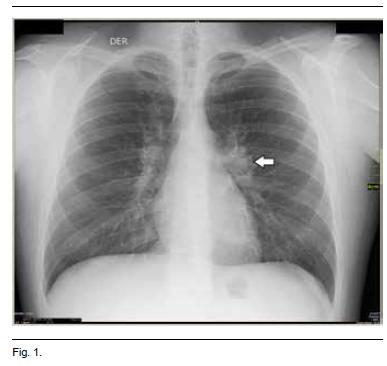

A nivel imagenológico se solicitaron radiografías de articulaciones tibiotarsianas y puños que fueron normales. La radiografía de tórax evidencio agrandamiento de los hilios compatible con adenomegalias (Figura 1).

Las linfadenopatias torácicas del síndrome de Löfgren típicamente se presentan a nivel hiliar bilateral y paratraqueal derecho. Muestran tendencia a resolverse en plazo de semanas en el 90% de los casos, con solo pocos casos descritos con persistencia y progresión(18).